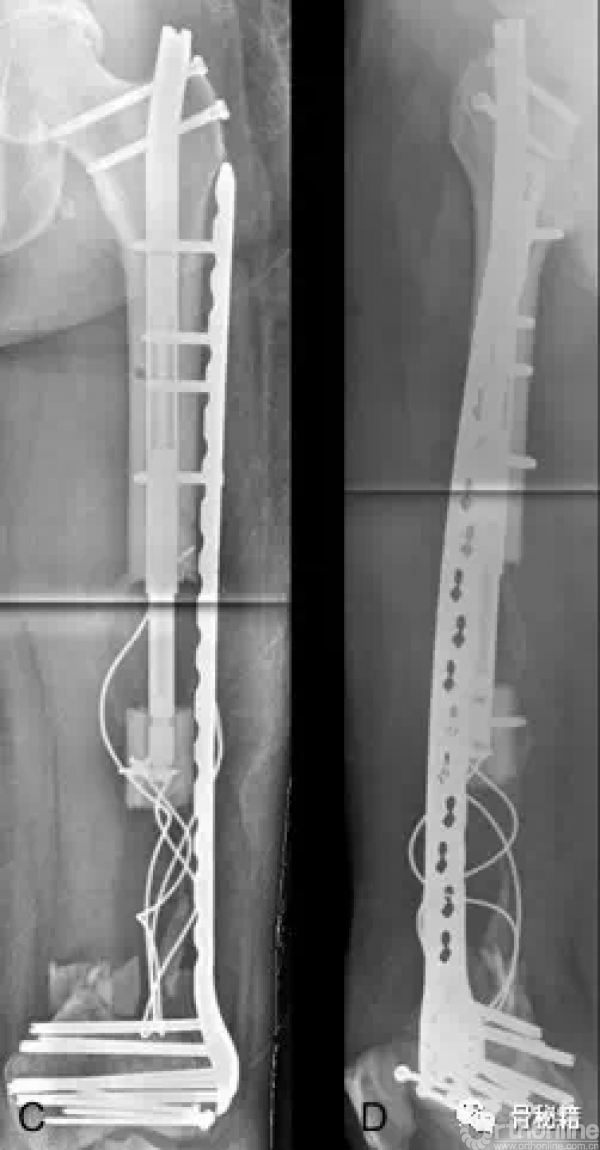

通过漫长的搬移,终于骨折断端接触了

更换全长的髓内钉来进行稳定骨折

术后13个月随访,骨搬移矿化良好

一根可延长髓内钉,就完成了整个手术

不用带外架,患者耐受度高

力线完美维持